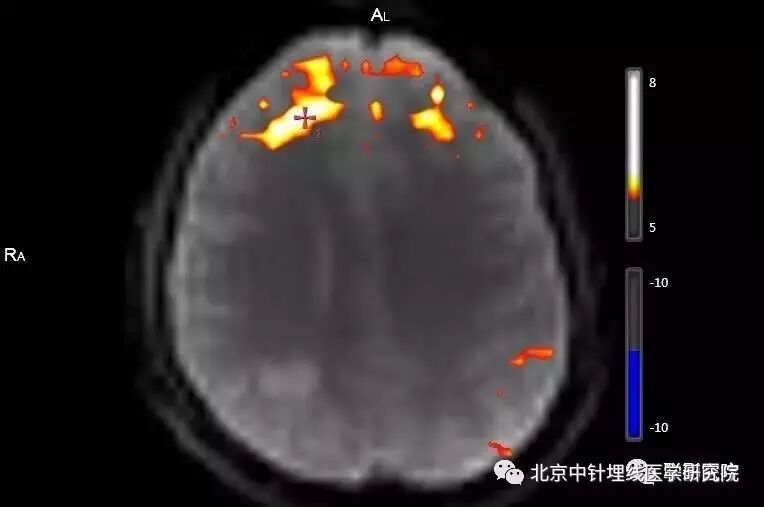

后处理的结果很快出来了,受试者的大脑额叶和边缘系统出现高信号,即显示被激活状态。詹松华教授推断,针灸百会穴可以通过影响大脑功能区的活动,对副交感神经和神经内分泌系统起到调节作用,从而起到改善胃肠功能的作用。

▲受试者大脑额叶和边缘系统呈现被激活状态